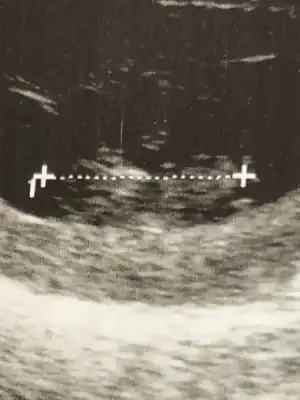

Sırtını dönmüş, erkek bu hehehe...Kizlar madem anlayan var benimkine de bisey soyleyin maksat eglence olsun catliyorum meraktan10 haftalik hali

Hadi bakalımSırtını dönmüş, erkek bu hehehe...

Yine yorumlayın size zahmet.

Eki Görüntüle 2144410 buda şimdiki hali

Eki Görüntüle 2144410 buda şimdiki hali

Canım bir çıkıntı var gibi geldi bu sefer ama benim gördüğümü doktor haydi haydi görürdü yani acaba kordon filan mı dedim o yüzden :)